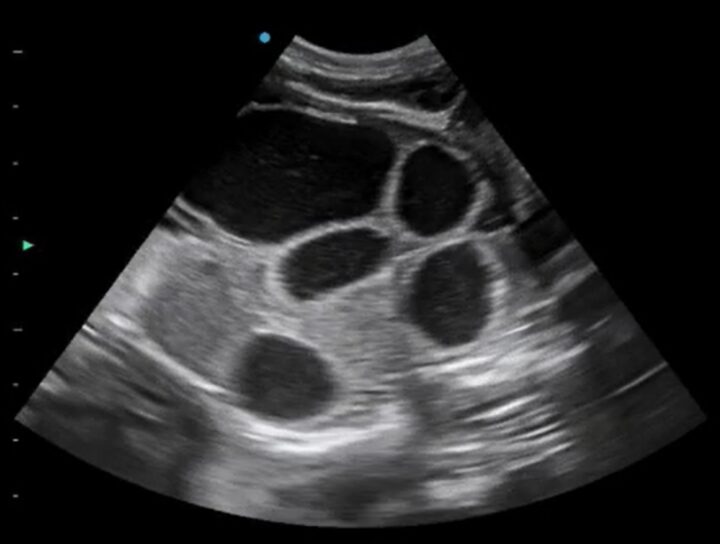

More advanced users may begin to spot foetal abnormalities, such as hydrocephalus, foetal anasarca or bowel obstructions, due to the ease at which ultrasound can image fluid (Figure 4). This is a clear advantage of the veterinarian performing scans in-house over the lay scanner, who would need to refer such findings.